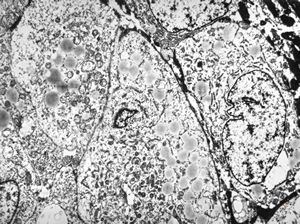

normal seromucinous salivary gland